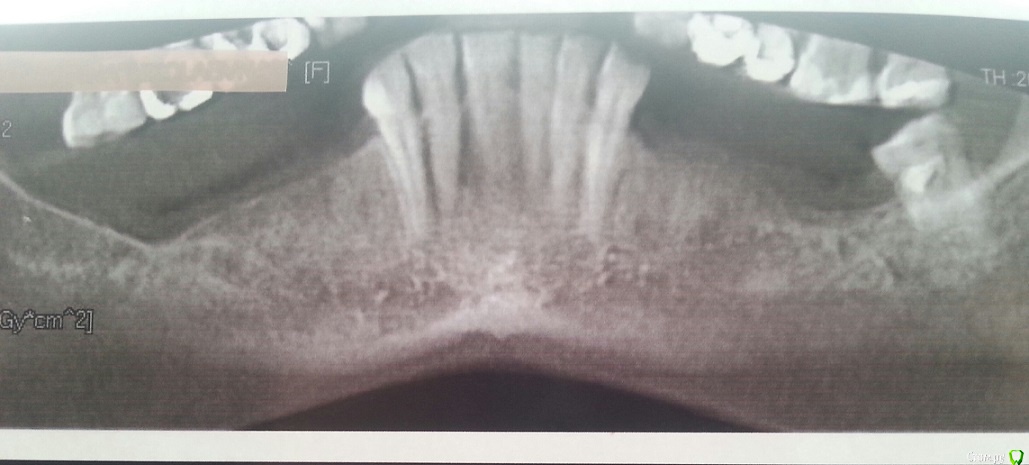

Очень нужен совет. На нижней челюсти всего 7 зубов. 31,32,33,38 и 41,42,43. Вопрос по имплантации находится в стадии разработки. Консультации, осмысления....  Пишу это, чтоб мне не говорили, что это предпочтительней всего. Сама знаю. На консультации у отропеда был предложен альтернативный вариант: бюгель на кламмерах. (Это если откажусь от имплантов).  Причем бюгель не на хромокобальтовом сплаве, а на золото-платиновом сплаве. У меня два вопроса. 1. Чем золото-платиновый сплав отличается от хромокобальтового? Кроме цены конечно. Чем он предпочтительней? 2. Меня почему-то очень смущает: достаточно ли опоры для установки бюгеля? И не будет ли он "болтаться"? На данный момент у меня съемник акриловый. Неудобный конечно, но сидит хорошо. И еще. Зубы у меня очень мелкие, невысокие, а 33 и 43 скошены. И как за них зацепляться, не представляю.

Чтобы понять сколько нужно опор, надо смотреть состояние оставшихся зубов, как во рту, так и по рентгеновскому снимку. Приложите панорамный снимок.

Как правило шести-семи опор достаточно при хорошем состоянии вышеуказанных.

Проблема в том что эти зубы ( передние) надо будет объединить в одну конструкцию коронками, чтобы шинировать и восстановить их по высоте( если здесь конечн не компенс форма стираемости). Если это делать и бюгель на платиновом сплаве( зачем?) то по стоимости это будет недалеко от имплантации